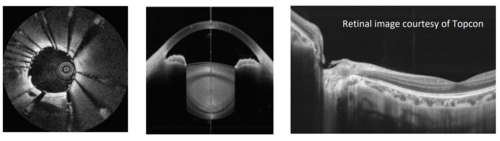

OCT LASER

OCT LASER (2)